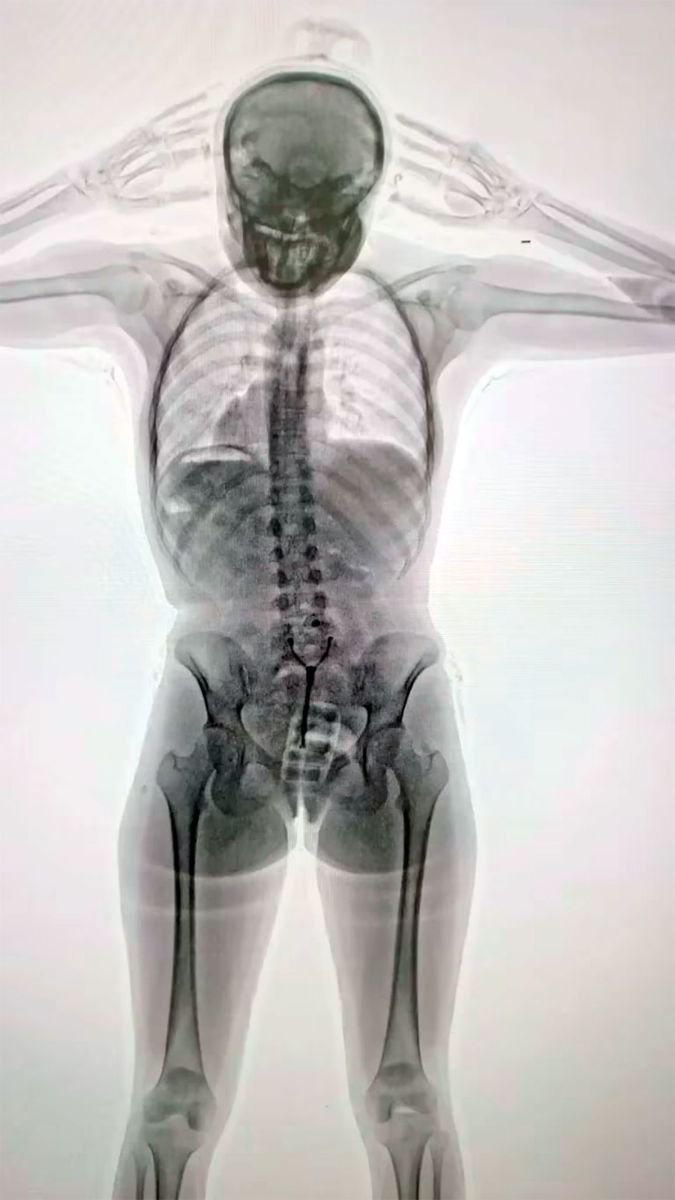

Imágenes son impactantes. La joven de 20 años que fue descubierta tras un control con equipo de rayos X en Ezeiza

Ante las consultas, la pasajera “respondió de manera incongruente y dubitativa”, lo cual levantó aún más las sospechas. Ante esta situación, agentes de la Policía de Seguridad Aeroportuaria (PSA), conjuntamente con funcionarios de la Dirección General de Aduanas y personal de AIRCOP, procedieron a realizarle un control corporal no invasivo mediante equipo de rayos X (Body Scan) y delante de la presencia de testigos.

La inspección dio pie a la revelación del delito: en las imágenes los efectivos observaron la posible presencia de elementos extraños en el organismo, concentrados en su zona genital.

En consecuencia, con la orden judicial en mano, la pasajera empezó a ser requisada hasta que en un momento confesó espontáneamente y manifestó que transportaba un paquete introducido vía vaginal. Concretamente, había introducido en su cuerpo un profiláctico con 11 cápsulas de cocaína, de aproximadamente 10 gramos cada una.

Como parte del procedimiento, la joven fue trasladada al Hospital de Ezeiza. Allí, bajo custodia de la PSA, estuvo incomunicada mientras evacuaba las cápsulas detectadas en las imágenes del escáner, las cuales finalmente fueron muchas más que 11: tenía otras 67 cápsulas en el sistema digestivo. En total, en su cuerpo llevaba 742 gramos de esa droga.